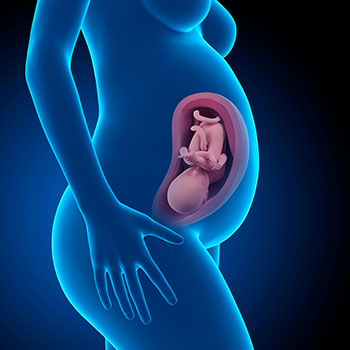

Na 34ª semana de gravidez o bebé mede cerca de 44 centímetros desde o cocuruto até ao calcanhar e pesa em média 2, 146 Kg.

Grávida de 34 semanas

Durante estas semanas o bebé vai adotar a posição que terá ao nascer. Geralmente, até finais do sétimo mês de gravidez vira-se de cabeça para baixo, que é a melhor e mais frequente posição.

Idade do feto: 32 semanas

Gravidez de 34 semanas

A partir das 34 semanas de gravidez, o tamanho da barriga vai ser devido cada vez mais exclusivamente ao bebé, o que se explica com a progressiva diminuição do líquido amniótico que agora está a ajudar os pulmões e os intestinos do bebé a maturarem e a controlar a sua temperatura, além de lhe fornecer as proteínas de que necessita.

Nesta altura, a quantidade de líquido que rodeia o bebé está no seu ponto mínimo e a placenta já deixou praticamente de crescer.

Um efeito da cada vez menor presença do líquido amniótico, bem como de que o bebé tenha cada vez menos espaço no útero, é que os seus pontapés e movimentos se vão tornar mais óbvios.

Nesta etapa, o útero chega a estar cerca de 14 cm acima do umbigo e tal faz com que os órgãos digestivos como o intestino, o fígado ou o baço se desloquem para cima e que, por isso, sintas dor, pressão ou comichão na zona das costas.